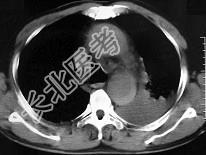

- 单项选择题男,58岁, 有高血压病史,突发胸背剧痛, CT扫描如图,其最可能的诊断为 ( )

E、主动脉夹层动脉瘤